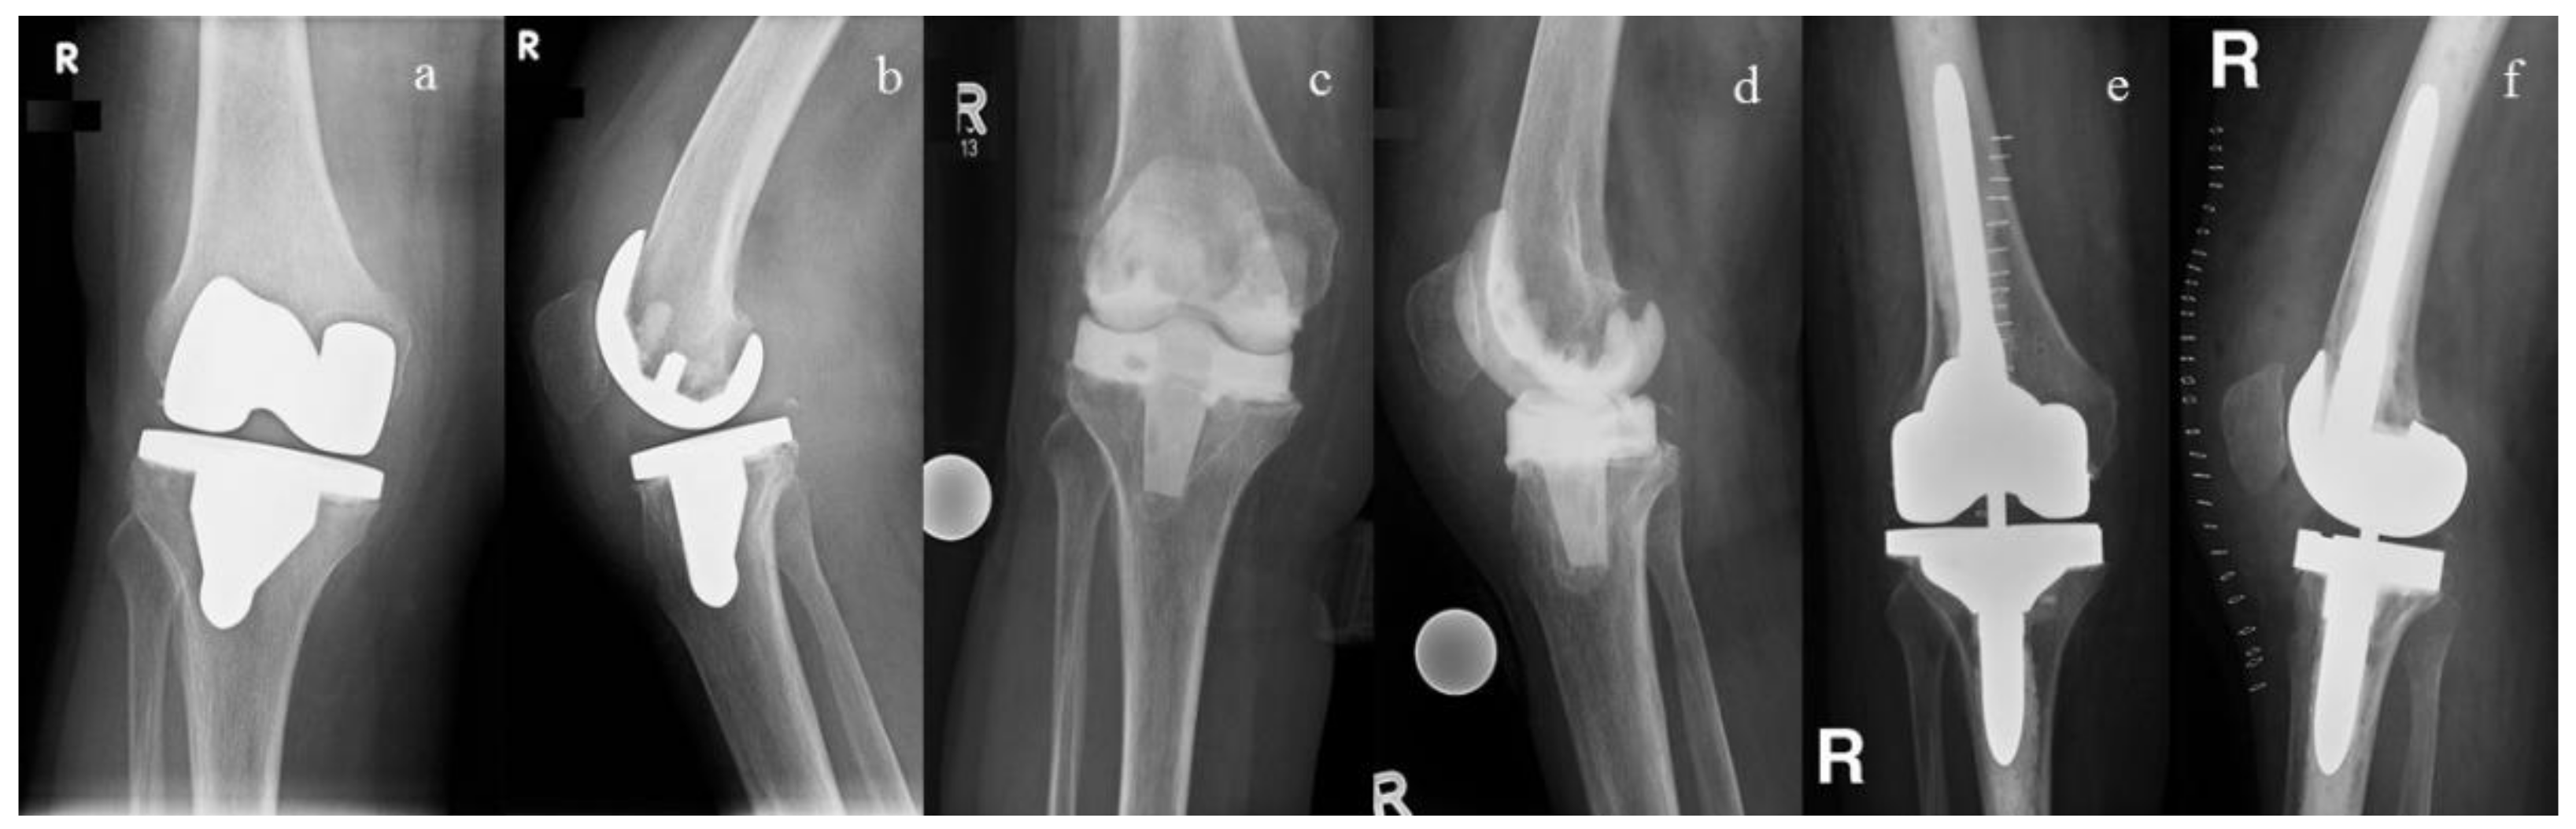

2.3. Antibiotic Impregnation of the Spacers/Beads and Resistance Rates

2.4. Clinical and Infection Outcome